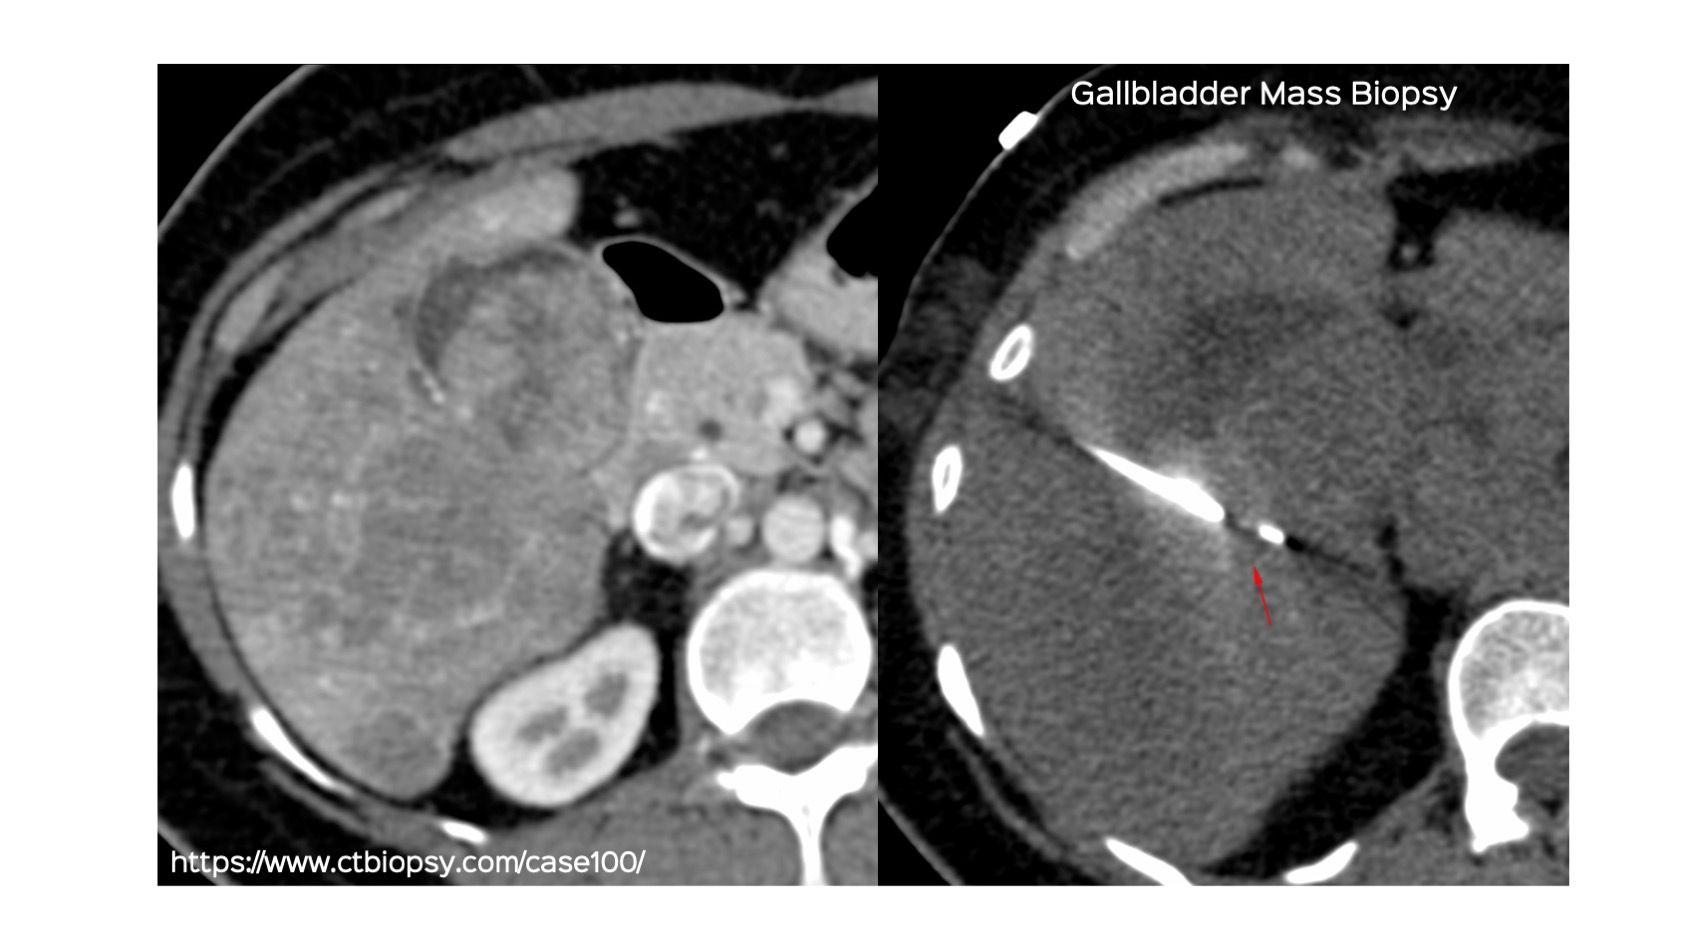

Case 100: Gallbladder Mass Biopsy

Bhavin Jankharia - 09 August 2022